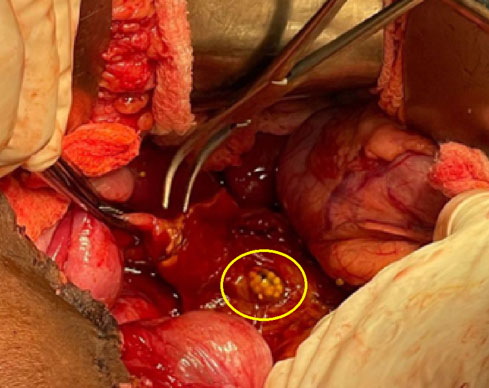

The patient arrived at the quaternary care hospital in poor condition, tachycardic, with fever, and signs of peritoneal irritation. Liver function was normal, with a C-reactive protein of 7.7 mg/dL, leukocytes of 10,700 mm3, and platelets of 512,000 mm3. An urgent exploratory laparotomy was planned due to suspected duodenal perforation. The surgery revealed free serous intrabdominal fluid, adhesions of the small intestine to the pelvis, a long appendiceal stump, inflammatory changes in the right retroperitoneum, and distal CBD necrosis with a secondary perforation due to an embedded gallstone, as observed in Figure 2. The gallbladder had a normal macroscopic aspect. Drainage of the peritonitis and release of the right colon through Toldt’s line and Kocher’s maneuver were performed to achieve adequate exposure of the duodenum and hepatic hilum, which showed a significant inflammatory process. Support from hepatobiliary surgery was requested during the intraoperative period, and a careful cholecystectomy was performed. Due to the condition of the bile duct, it was not possible to perform a primary raffia or management with a T-tube. Therefore, a distal bile duct resection and reconstruction with Roux-en-Y hepaticojejunostomy were opted for.

Figure 2: Gallstones within the perforated common bile duct.